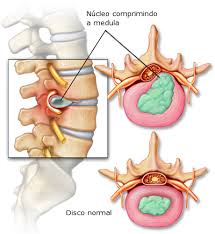

Entre duas vértebras vizinhas na coluna existe uma estrutura chamada disco intervertebral que funciona como um amortecedor, como forma de diminuir o impacto e a sobrecarga de uma vértebra sobre a outra.

Na porção central do disco há um material mole chamado de núcleo pulposo e que é circundado por um tecido mais resistente, que é o anel fibroso.

Em algumas situações em que o disco torna-se enfraquecido ou quando ocorre uma sobrecarga da coluna (exemplo: carregar peso) há uma ruptura do anel fibroso e o núcleo pulposo ultrapassa os seus limites, sofrendo uma herniação.

Surge aí uma hérnia de disco.